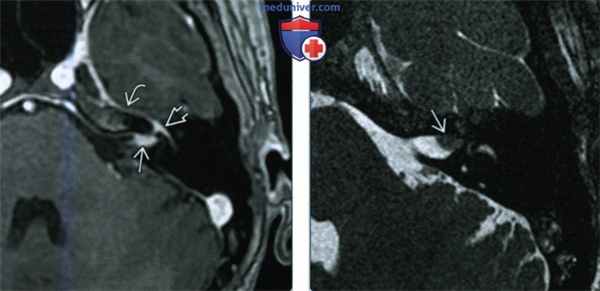

о Патологическое контрастирование ЧН VII ± ЧН VIII в области дна внутреннего слухового канала, а также перепончатого лабиринта (полное или частичное) на МРТ Т1 С+

о Линейное или веретеновидное контрастирование ВСК

(Справа) При аксиальной MPT Т1 ВИ С+ FS у пациента с СРХ определяется линейное контрастное усиление ЧН VII в области дна ВСК с распространением на лабиринтный и барабанный сегменты. Верхний преддверный нерв также контрастируется в области дна ВСК и в преддверии.

(Слева) При аксиальной МРТ SPGR С+ определяется контрастное усиление дна ВСК слева, а также лабиринтного сегмента, коленчатого ганглия, переднего барабанного сегмента ЧH VII. Накапливает контраст и большой поверхностный каменистый нерв (ветвь ЧH VII), расположенный вдоль переднего края вершины пирамиды.

(Справа) При аксиальной MPT Т2ВИ FS с увеличением у этого же пациента в области дна ВСК визуализируются утолщенные, воспаленные ЧН VII и ЧН VIII, изоинтенсивные головному мозгу.